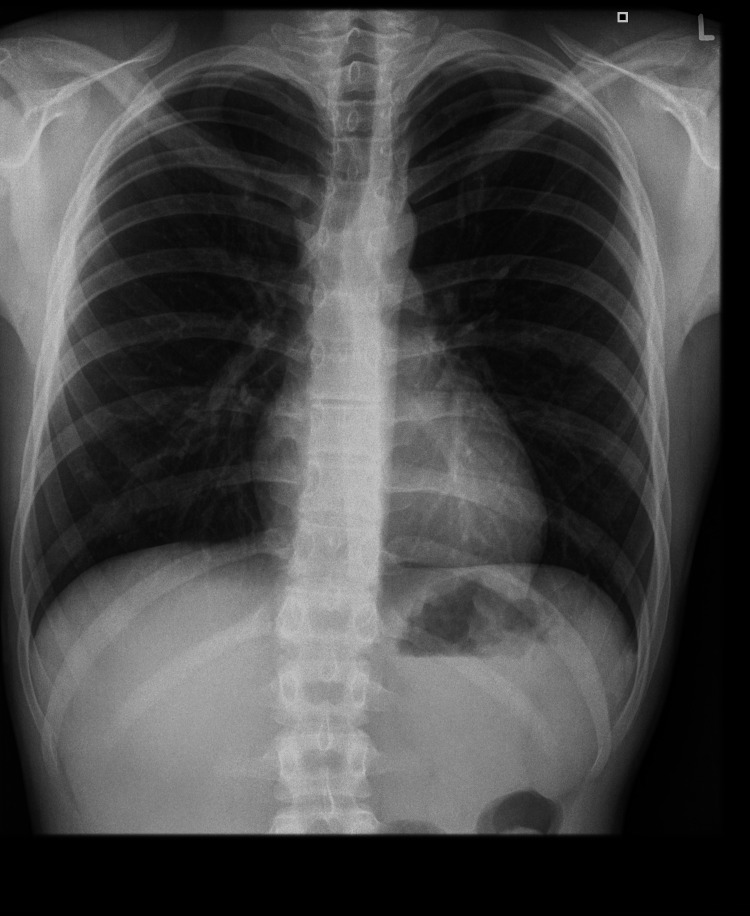

On admission, the patient’s general condition was good, weight was 56.08 kg (10-25 percentile), height was 173 cm (10-25 percentile), and BMI was 16.9 (75-90 percentile). No significant deviations were observed on physical examination. On the day of admission, laboratory tests, abdominal ultrasound (Figure 1), chest X-ray (Figure 2), lactose test, and fecal calprotectin levels were normal. However, in the afternoon, repeated vomiting was observed, initially with bile, then with large amounts of saliva, accompanied by agitation, profuse sweating, motor restlessness, and hand tremors; the patient was also aggressive toward his mother and medical staff. Attention was drawn to the boy’s inadequate behavior: fear, calling for his mother, then aggression, and declaring a desire to escape from the ward. For this reason, urine toxicology tests were ordered, in which the presence of tetrahydrocannabinol was confirmed. Upon conducting a more thorough investigation, the patient confirmed the use of the substance a few days before admission to the clinic. A conversation was held with the mother regarding the child’s use of psychoactive substances, and she declared that she knew about the problem and for this reason, attended a psychologist with the child. Each time the onset of symptoms occurred after ingestion of food xenobiotics (including alcohol and marijuana), the patient confirmed the temporal relationship between the onset of symptoms and ingestion of xenobiotics. In addition, a history of cigarette smoking is currently denied. The patient confirmed a temporal relationship between psychoactive substance use and alcohol consumption.